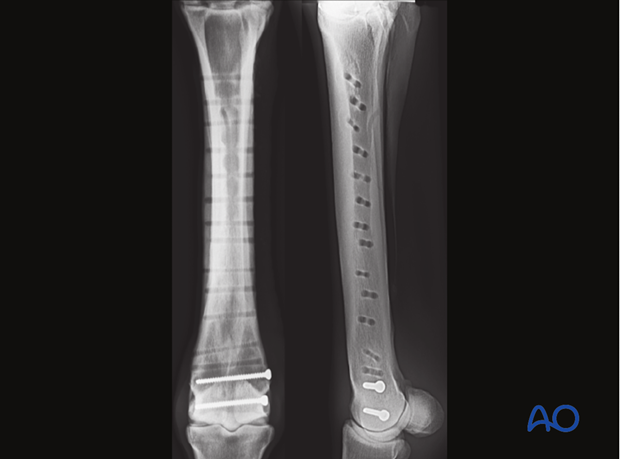

Documenting radiographs are obtained.

Horses are usually kept under stall rest and hand-grazing only for at least 60 days followed by hand walking or machine walking exercise for an additional 30 days before removing the plate. The two distal screws are usually left in the bone.

All incisions are closed with simple interrupted skin sutures and a padded bandage applied. The distal two screws that were inserted before plate application are left in place.